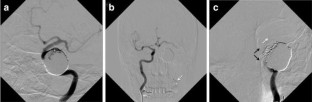

Fig. 4